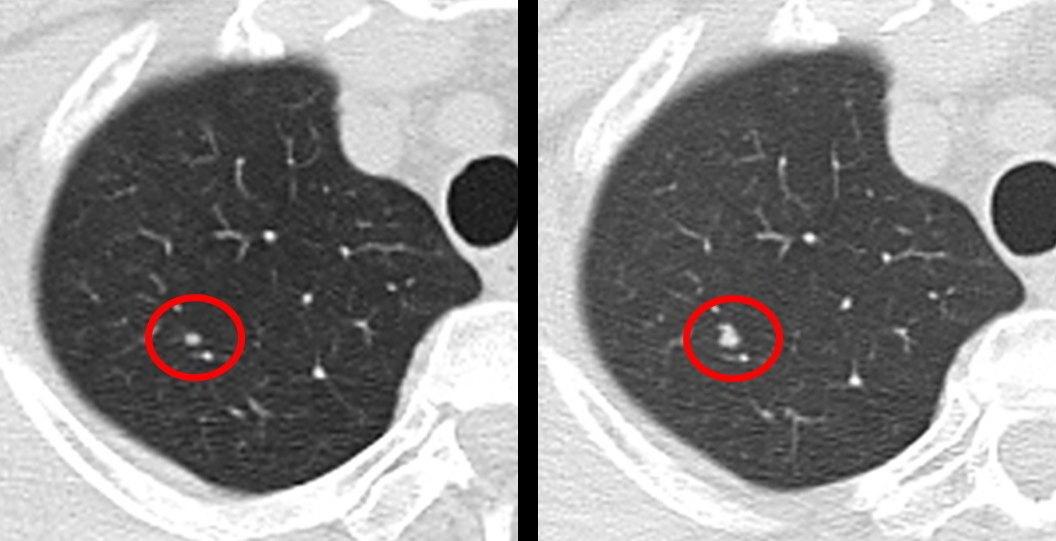

那么恶性结节,怎么样才能快速发现呢?首先检查报告的时候就能看出端倪,第一直径比较大;其次是从发现之后短短几个月,结节外形会有新的变化,这种情况就要及时治疗了。临床给出的经验是,直径在10毫米以下的,建议患者每三个月复查一次。

通常检查报告显示,边界清晰,形状比较规则,没有出现奇怪的形状;而恶性的话,检查报告会提示,形状会出现毛刺,分叶,小泡征等信息;这种情况就需要复查,排除是否存在恶性的可能。

大家可以想象一下,超过1.5cm的结节,到底有多大。通常正常体检的结果,80%都属于良性结节,形状大小会小于1cm。如果超过1.5cm,这种就是实性结节了。这个时候有很大概率是肺癌。这里值得提醒大家,结节大小大于8mm,并且报告单提示着“混合磨玻璃结节”这个关键词的话,也要注意是否有恶性的可能。